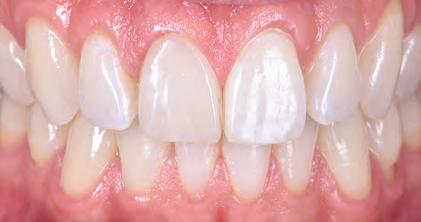

FIGURE 2: Initial treatment focussed on patient-driven improvements in oral hygiene, supplemented by professional mechanical plaque removal and ongoing fourmonthly supportive periodontal therapy. The patient demonstrated a sustained commitment to oral health behaviour change, as evidenced by the establishment of a robust, pale, pink and stable gingival architecture.

At this early stage of diagnostic work-up, prior to any operative intervention, the clinician and the technician can now communicate to each other and, most importantly, to the patient, in an understandable visual rhetoric, a precise end goal of treatment from which a meeting of the minds may be achieved (Figures 6 and 7).5

FIGURE 6: Prior to any irreversible and biologically expensive operative intervention, the tripartite stakeholders (patient, clinician and dental technician) of the reconstruction can achieve a precise meeting of the minds in a universally understandable visual rhetoric regarding the intended end goal of treatment.

FIGURE 7: Close-up extra-oral and intra-oral views illustrating satisfying contours of a proposed definitive restoration.